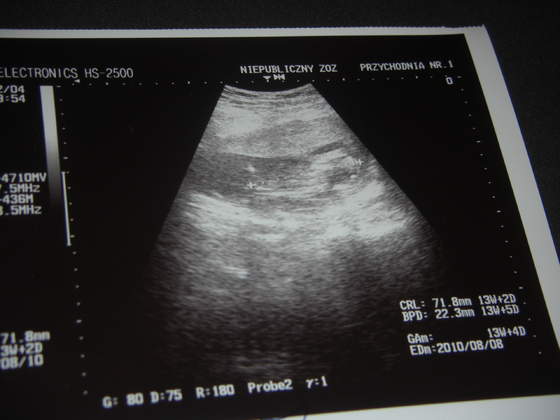

A oto moja dzidzia zdjęcie zrobione 02 luty !!!!!

Ma 3,5 cm !!!!! Słuchałam bicia serduszka, no niesamowite przeżycie!!!!!Prawda????